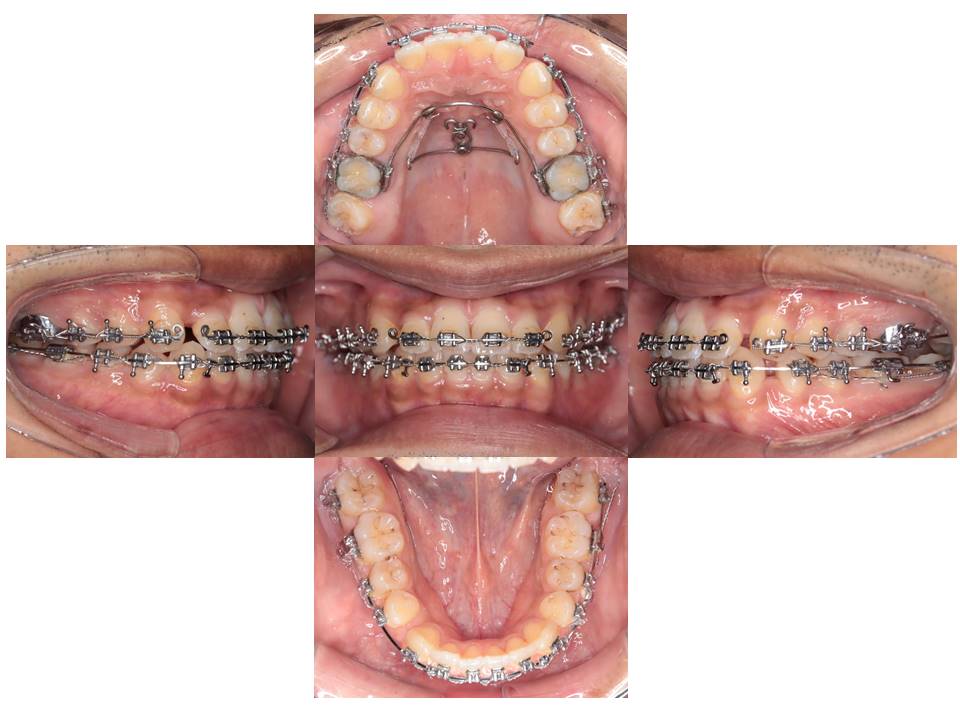

装置撤去時(治療終了)